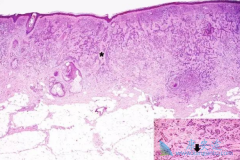

经常摄入含咖啡因的饮料或可降低基底细胞癌的患病风险

美国哈佛大学医学院研究人员日前完成的研究显示,常喝含咖啡因的咖啡有助于降低患常见皮肤癌—— 基底细胞癌 的风险。研究人员分析了参加“健康职业跟踪研究”和“护士健康研究”的11.2万人为期20多年的数据后发现,每天饮用3杯以上含咖啡因咖啡的女性患 ...